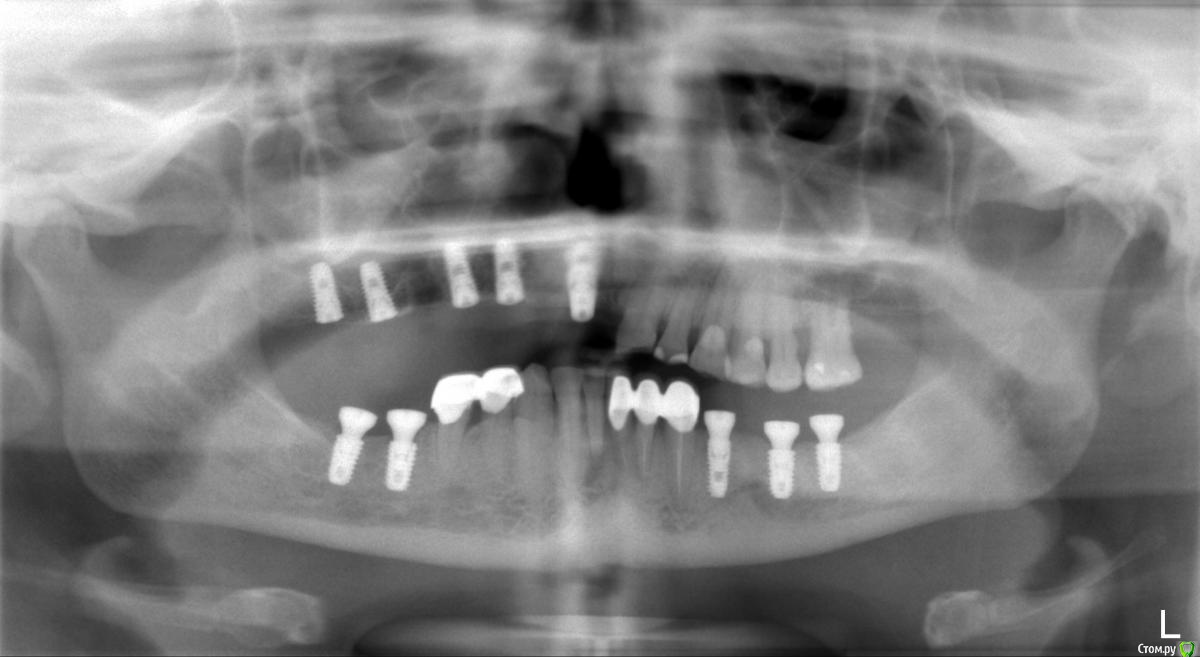

Liliya_imp Опубликовано 11 декабря, 2016 Поделиться Опубликовано 11 декабря, 2016 (изменено) Доброго времени суток, коллеги.В первый раз буду делать тотальную работу, поэтому ваша помощь и рекомендации в последовательности действий не помешает.Буду благодарна всем советам.Пациентка обратилась с уже существующей на снимке ситуацией. Не закончила протезирование в предыдущей клинике в связи с переездом. Очень нужна ваша помощь и поддержка молодому врачу Изменено 11 декабря, 2016 пользователем Liliya_imp Ссылка на комментарий

doktor vv Опубликовано 13 декабря, 2016 Поделиться Опубликовано 13 декабря, 2016 Кривая Шпее совсем плоха с левой стороны(Возможно и ортодонтия потребуется Ссылка на комментарий

suballex Опубликовано 16 декабря, 2016 Поделиться Опубликовано 16 декабря, 2016 Кривая Шпее совсем плоха с левой стороны(Возможно и ортодонтия потребуетсяМне кажется, это сошлифовка. Восстановить ортопедической реставрацией и кривая будет в первозданном виде. Но, подтвердить может только вакс-ап Ссылка на комментарий

алекс 100 Опубликовано 20 декабря, 2016 Поделиться Опубликовано 20 декабря, 2016 Странное положение импл.в обл. 1.1,лучше воск посмотреть с пациентом,по воску и препаровка. Дальше все как всегда. Ссылка на комментарий

molchanoff Опубликовано 22 декабря, 2016 Поделиться Опубликовано 22 декабря, 2016 25 и 26 на выход для начала Ссылка на комментарий